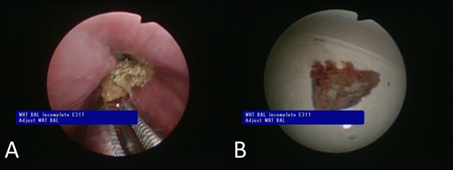

由於病人氣管內異物已經引發嚴重發炎反應,被周圍氣管內肉芽組織卡住,在軟式支氣管鏡輔助下無法以鼠牙鉗和圈套器取出異物。因此胸腔外科醫師改用腹腔鏡器械5mm的腹腔鏡抓取鉗,在軟式支氣管鏡的引導下,成功抓取並取出中間支氣管中的異物(圖二)。病人術後恢復良好,呼吸道症狀在氣道異物移除之後明顯改善。

圖二、腹腔鏡器械在軟式支氣管鏡的引導下,成功抓取並取出中間支氣管中的異物